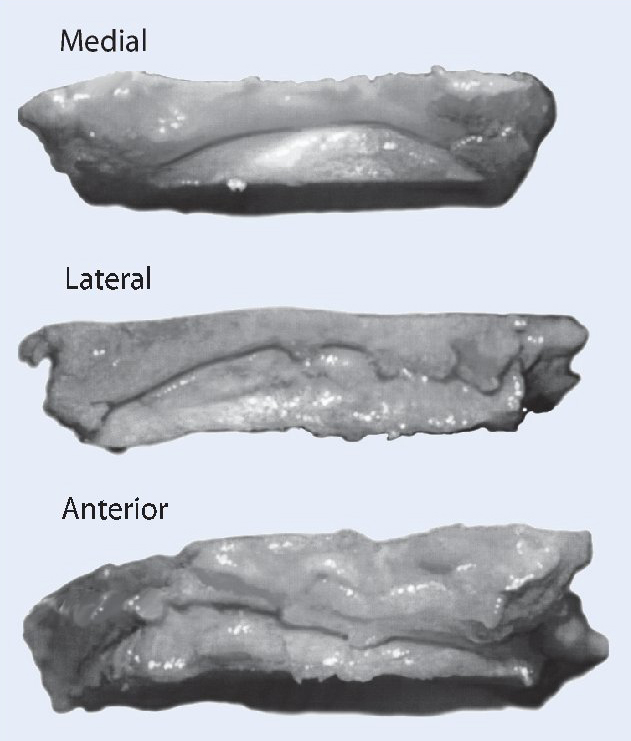

Fig. 5 Decortización de la cara medial del peroné distal con sierra oscilante. Esto aumenta la potencia biológica de la refijación.